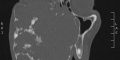

“L’intervento è stato molto complesso-dice il professore Moschella- perché il tumore aveva già divorato il seno mascellare, il naso, parte dell’occhio, ma soprattutto entrava nella base cranica e posteriormente veniva a contatto con la colonna vertebrale, quindi ci sono voluti mesi di studio per poterlo affrontare, cambiando spesso strategie chirurgiche fin quando non ci siamo convinti di quale fosse la strada giusta, e dopo venti ore di sala operatoria possiamo dire di esserne soddisfatti”.